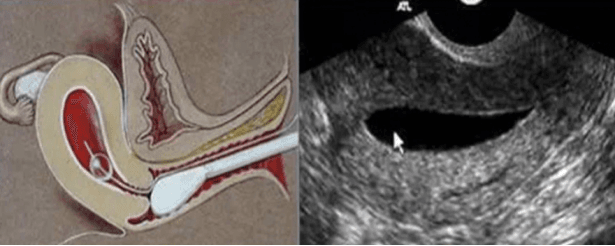

也称生理盐水宫腔声学造影(SIS)检查技术,是通过宫腔置管向宫腔内注入生理盐水使宫腔扩张,在超声监测下动态观察宫腔内情况的一种超声检查技术。宫腔水造影检查能够清晰直观的显示宫腔情况,有着操作安全便捷、检查费用低廉、检查过程无痛苦、可重复性高等特点。在球囊逐步缩小并撤管的过程中,从宫腔底部到宫颈外口都清晰可见,检查优势一目了然。